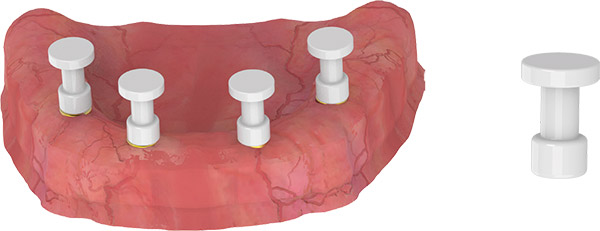

IMMEDIATE RESTORATION

- Manually mount and screw the temporary abutments onto the Multi-Unit and Multi-Base Abutments.

- Perforate the denture and prepare it to fit the temporary abutments so that the prosthesis does not put pressure on the mucosa.

- Manually assemble the healing caps by applying a slight torque (5-10 Ncm) by finger power.